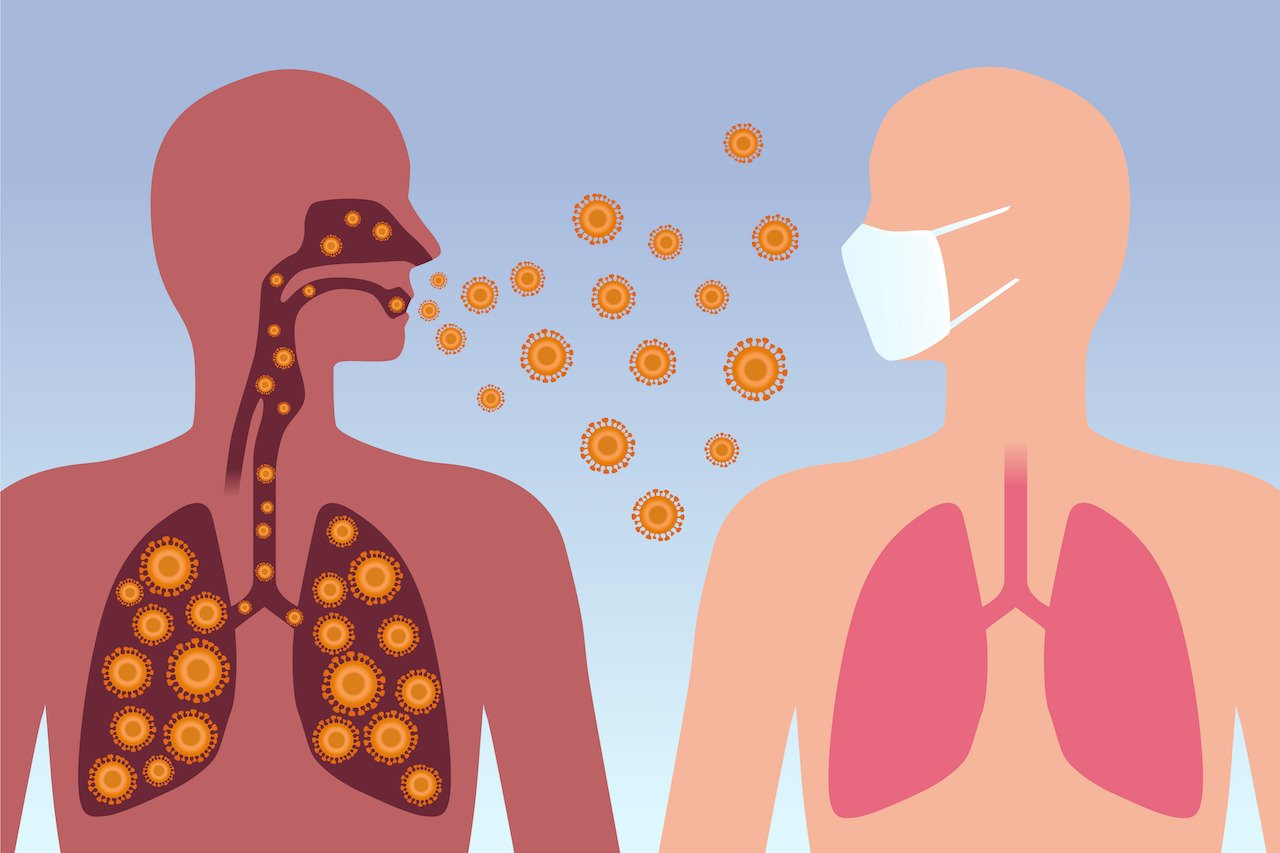

Поражение легких при коронавирусе

Легкие зараженный Ковидом

Бактерии и вирусы в легких

Коронавирус пути передачи воздушно-капельный